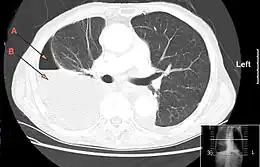

En général, le scanner thoracique se fait en seconde intention, à la recherche d'une cause et de lésions associées (en dehors de l'infection)[20]. Il permet également d'explorer la morphologie de l'épanchement, et notamment de rechercher la présence de cloisonnements ou d'enkystement avant drainage pleural ou chirurgie. Cela permet de guider le geste et d'éviter une plaie pulmonaire lors de sa réalisation.